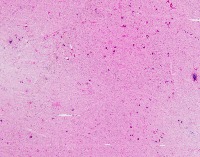

Medical Diagnostics: geckler5 can be used in healthcare facilities to analyze images of tissue samples, blood smear slides, or other medical images to detect the presence and distribution of White Blood Cells (WBC) and Erythrocyte Hemoglobin Concentration (EHC). This can aid in diagnosing diseases such as infections, anemia, or leukemia.

Research and Development: Scientists working in the field of hematology or immunology can use geckler5 to analyze large datasets of blood samples in their research studies. This can help them better understand blood cell morphology, variations, and concentrations in different conditions, ultimately leading to new medical discoveries.

Pharmaceutical Testing: The pharmaceutical industry can utilize geckler5 to analyze the effects of new drugs or treatment methods on WBC and EHC levels. This would allow researchers to monitor the efficacy, side effects, and other critical factors for drug trials and approval processes.

Educational Purposes: Educational institutions teaching medical or biological courses can implement geckler5 as a learning tool, helping students to identify and differentiate between various blood components. This can enhance their understanding of blood cell compositions and related medical conditions.

Blood Donation Centers and Blood Banks: geckler5 can be employed to assess the quality of blood donations in terms of WBC and EHC levels. This automated analysis would help staff ensure that donated blood meets necessary standards and is safe for transfusion into patients.